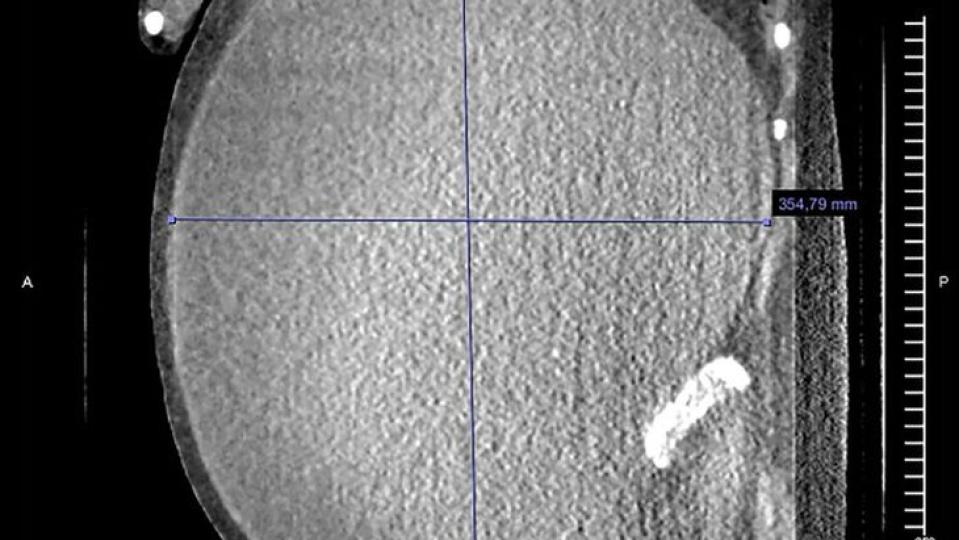

Лекарите й направиха обстойни прегледи и установиха, че на десният яйчник на жената има образувала се огромна киста с размер 40 см. в диаметър и тегло около 5 килограма. Те обясниха късната диагноза с липсата на образование и ниското материално състояние на жената. Именно заради това тя не е потърсила по-рано медицинска помощ.

Операцията е продължила шест часа, а специалистите изпомпват 37 литра гъста кафява течност от кистата, след което я отстраняват от матката и яйчниците на пациентката.